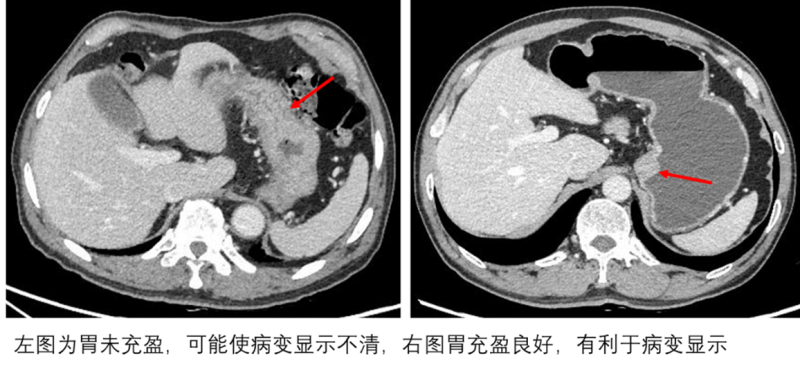

3.造成假象误诊:未充分被液体撑开的肠壁会在图像上显示异常增厚,可能被误认为肠炎或肿瘤;而真正有问题的肠壁增厚,也可能因准备不充分而显示不清。

因此,肠道准备的核心目标十分明确:最大限度清除肠道内的残渣和气体,并通过饮用特定液体使肠腔充分扩张。只有这样,原本蜷曲褶皱的肠壁才能被完全展开,像一张平整的地图般清晰呈现其真实状态,帮助医生准确捕捉每一处细微病变。